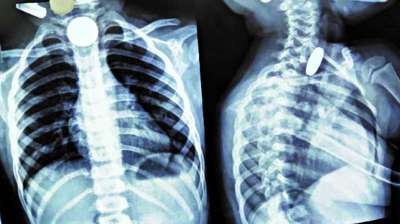

खिलौना नहीं सिक्का था! बच्चे ने निगले 5-10 रुपये के सिक्के, डॉक्टरों ने ऑपरेशन कर निकाले

24 Jul, 2025 04:09 PM IST | STORYLIVE.IN

दिल्ली : दिल्ली के एक सरकारी अस्पताल के डॉक्टरों ने 12 वर्षीय बच्चे की जान बचाई है। बच्चे ने पांच और दस रुपये के तीन सिक्के निगल लिए थे। सिक्के...